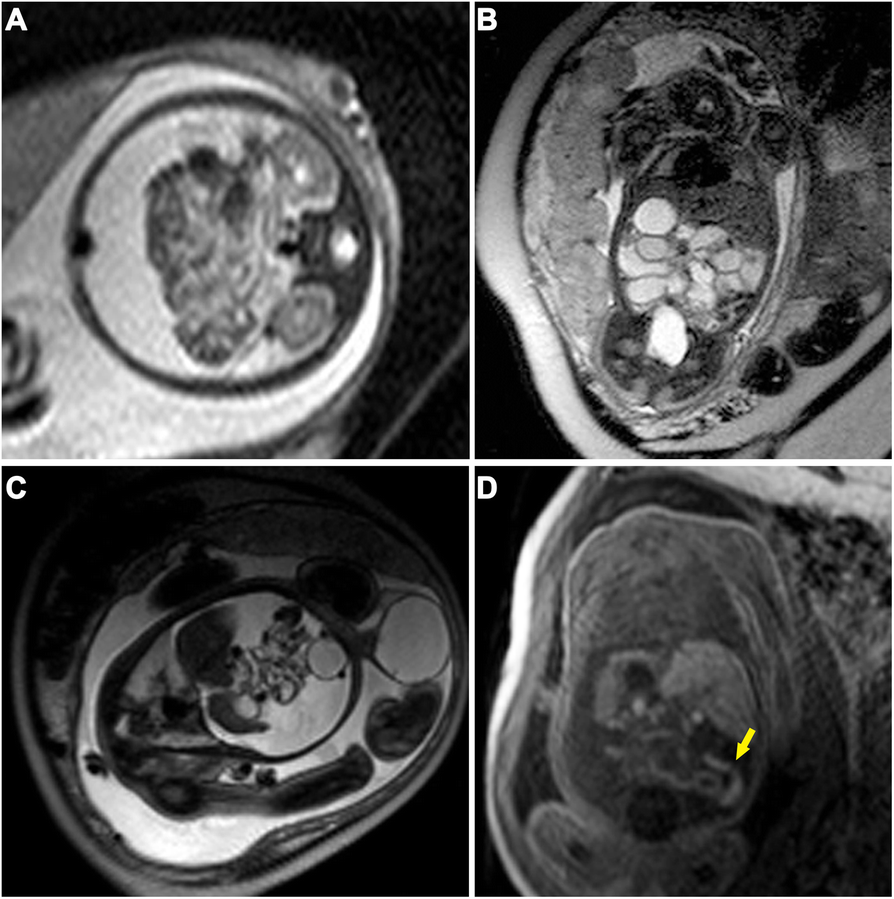

Fig. 2

Fetal MRI findings of meconium peritonitis in two fetuses receiving surgery. a-b A 30-week-old fetus with MP. A transverse 1.5-T T2-weighted image (TR = 15,000 ms, TE = 120 ms) indicates a large amount of ascites and gathering bowel loops (a) and dilated bowels (b). C-D. A 35-week-old fetus with MP. A sagittal 1.5-T T2-weighted image (c, TR = 15,000 ms, TE = 120 ms) reveals a high amount of free ascites in the peritoneal cavity, gathering and distortion of poor filled small intestines, and significant swelling in the left scrotum. A coronal T1-weighted image (d, TR = 234 ms, TE = 4.6 ms) shows distal micro-colorectum (yellow arrow)